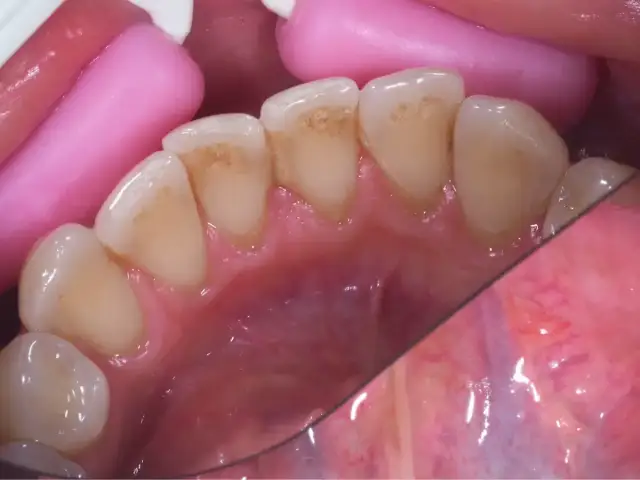

Ciemny osad na zębach - Czy to próchnica? Usuwanie i profilaktyka

Ciemny osad na zębach - czy jest groźny? Dowiedz się, skąd się bierze, jak go usunąć w gabinecie i skutecznie zapobiegać nawrotom. Sprawdź nasz poradnik!